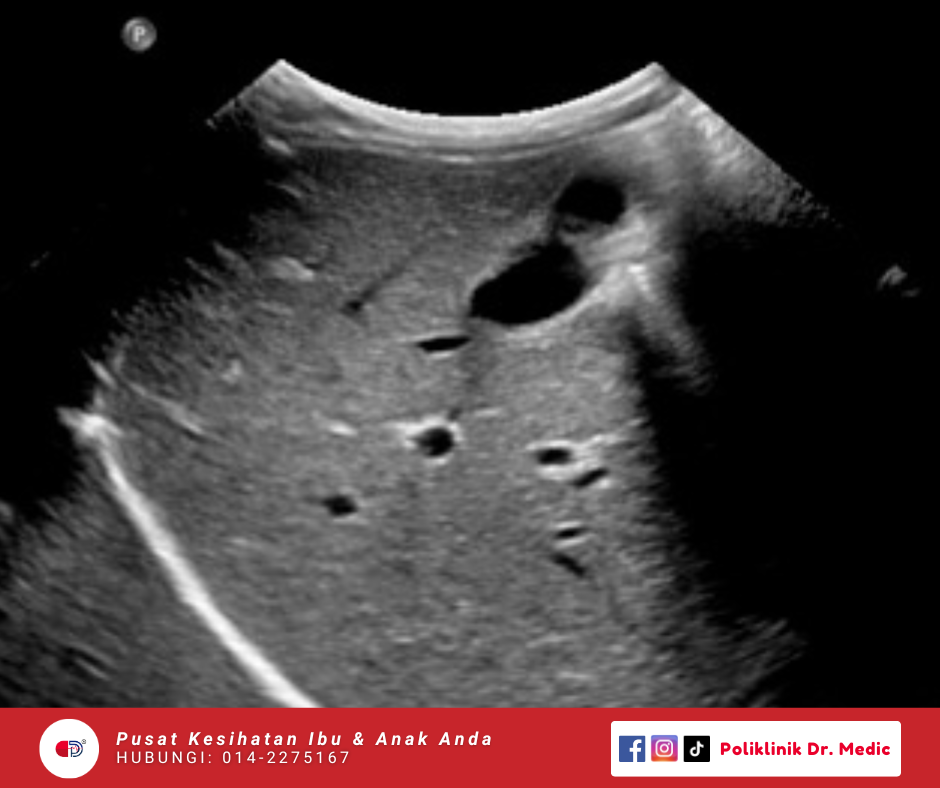

abdomen Scan

Pemeriksaan untuk hati, pundi hempedu, saluran hempedu, pankreas, limpa, aorta, buah pinggang, saluran kencing dan prostat. Sesuai sebagai saringan kesihatan berkala terutamanya bagi mereka yang jantina lelaki.

RM128